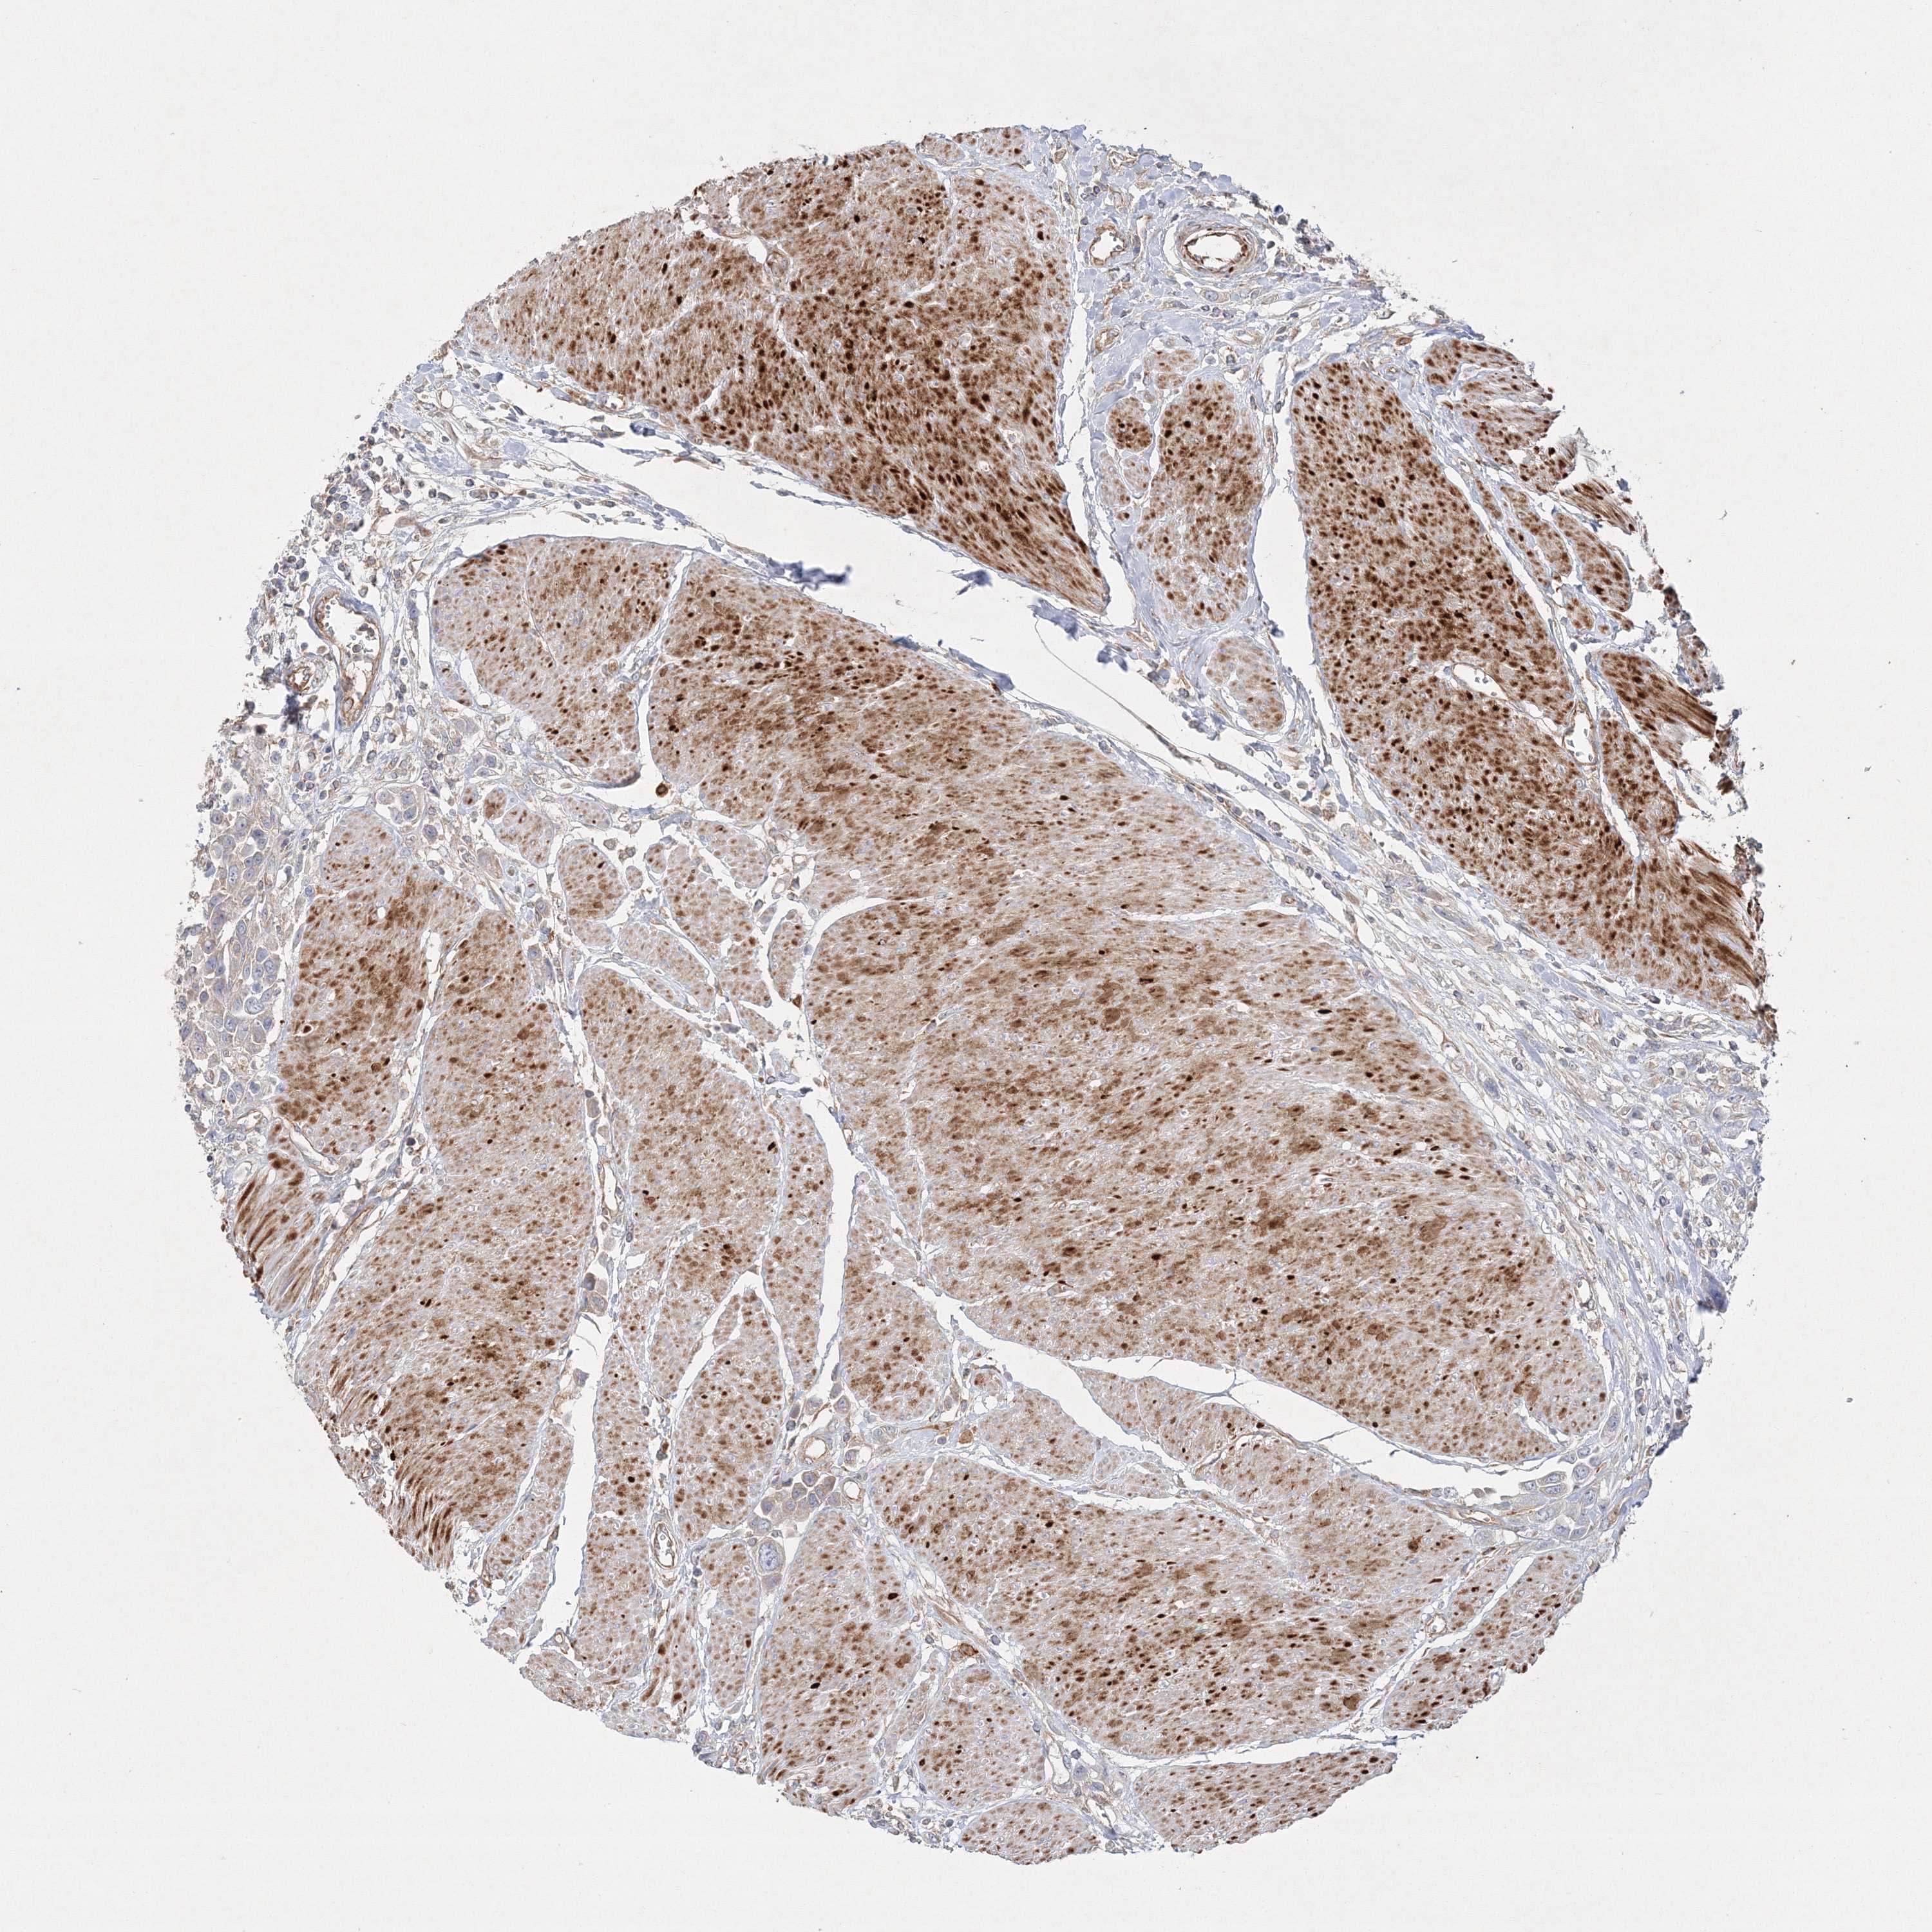

UROTHELIAL CANCER - Protein expressioni

A mouse-over function shows sample information and annotation data. Click on an image to view it in a full screen mode. Samples can be filtered based on level of antibody staining by selecting one or several of the following categories: high, medium, low and not detected. The assay and annotation is described here.

Antibody stainingi

Antibody staining in the annotated cell types in the current human tissue is reported as not detected, low, medium, or high, based on conventional immunohistochemistry profiling in selected tissues. This score is based on the combination of the staining intensity and fraction of stained cells.

Each image is clickable and will lead to virtual microscopy that enables deeper exploration of all samples and also displays staining intensity scores, fraction scores and subcellular localization as well as patient and tissue information for each sample.

Antibody HPA037376

Antibody HPA037565

Staining

High

Medium

Low

Not detected

Intensity

Strong

Moderate

Weak

Negative

Quantity

>75%

75%-25%

<25%

None

Location

Nuclear

Cytoplasmic/membranous

Cytoplasmic/membranous,nuclear

Urothelial carcinoma, Low grade

Urothelial carcinoma, High grade